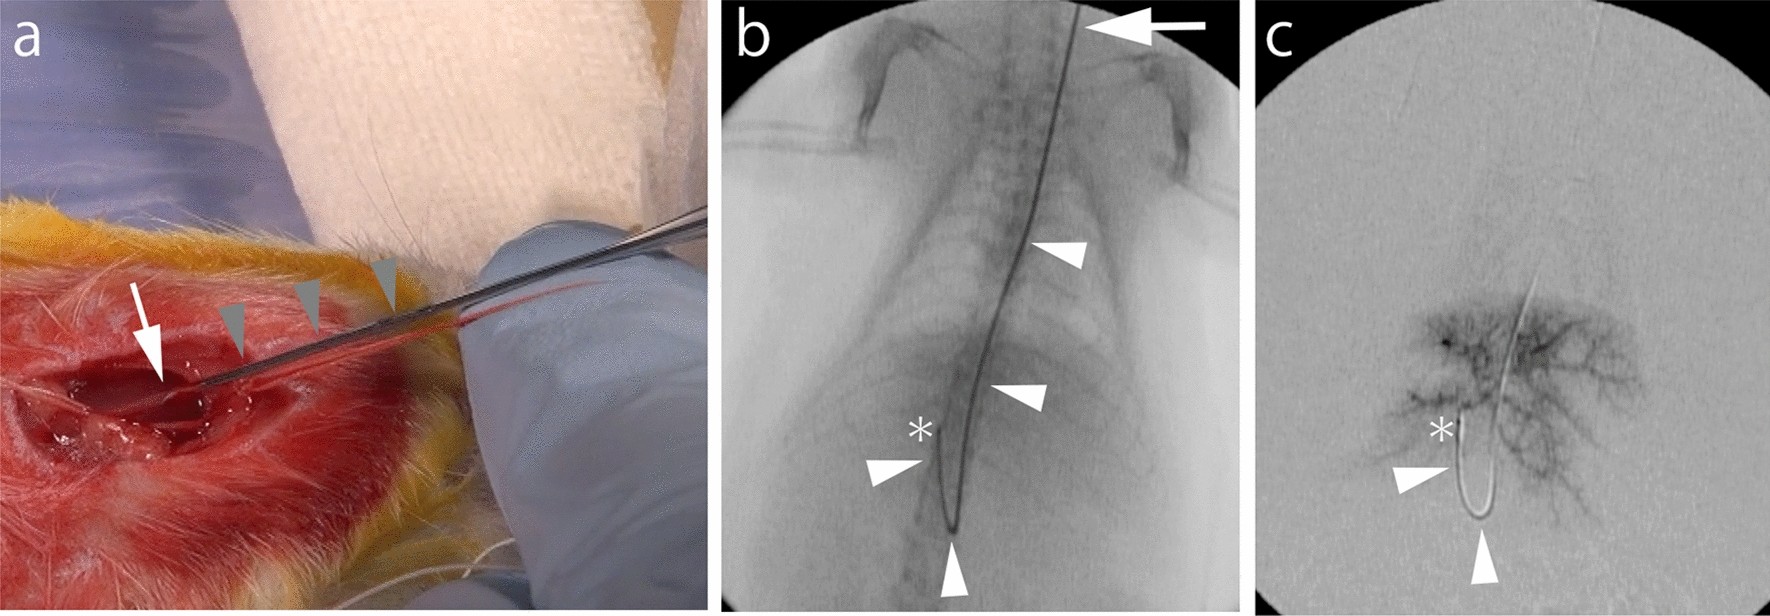

Figure 1

Interventional procedure. (a) 22-gauge intraarterial catheter (gray arrowheads) is punctured into the left common cervical artery (white arrow). (b) A 1.6-Fr micro-catheter with a 0.014-inch guidewire (white arrowheads) are inserted into the proper hepatic artery (asterisk). The left common cervical artery is located at white arrow. (c) Digital subtraction angiography via the proper hepatic artery (asterisk). Intrahepatic arterial blood vessels were depicted. A 1.6-Fr micro-catheter is indicated by white arrowheads.